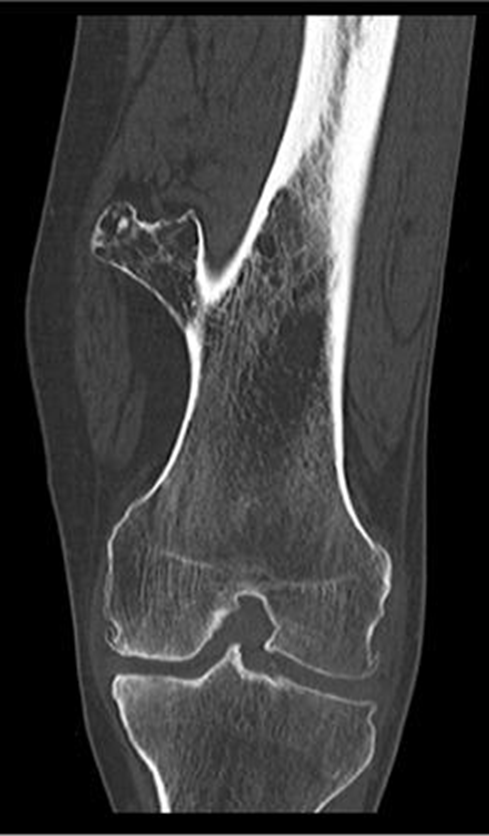

Osteochondroma

(Exostosis)

Benign projection of bone with a cartilaginous cap

Cause: idiopathic, hereditary

Complications: may turn malignant, pain, fracture of stalk

Radiographic Appearance: long axis of bone growth runs parallel to the parent bone and points away from nearest joint

Technical: No manual exposure factor change

Prognosis: Good, surgery only needed when there are mechanical

impingements

Stellate Fracture

•Fracture lines radiate form a central point of injury with a star like pattern

•Cause: Trauma - falling onto knees, knees hitting dashboard

•Complications: pain, weakness, infection, stiffness

•Radiographic appearance: comminuted fracture with a star like pattern

•No manual exposure factor change

• Prognosis/Treatment – Non operative and Operative

Travsverse displaced subtrochanteric fractrue proximal right femur